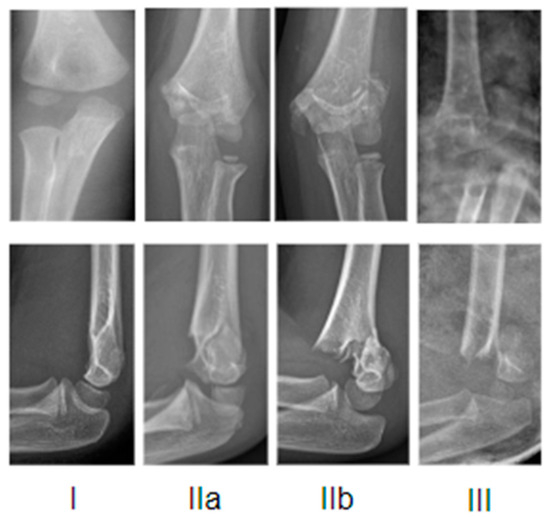

The radiographic Gartland’s classification modified by Wilkins is the most commonly used to describe the fracture pattern: I, IIa, IIb, and III (Figure 1).

In type I fractures, the fracture line is not easily identifiable and the sign of fat pads can help in making a diagnosis; it may be an occult fracture and the signs of healing could become visible at radiographic follow-up. In type II fractures, the integrity of the posterior cortex is maintained by a thick intact periosteum, but there is angulation of the bone fragments and the anterior humeral line falls anterior to the middle third of the capitulum (in type IIa, there is angulation without rotation; in type IIb, there is rotational and/or translational displacement). Type III fractures are complete and displaced; the direction of displacement is often postero-medial, more rarely postero-lateral.

Figure 1. Exemplificative X-rays representation of Gartland classification.